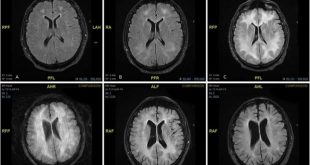

در این تحقیقات که با آزمایش روی ۱۴۰ بیمار مبتلا به SPMS انجام گرفت، بیماران به دو گروه تقسیم شدند.، گروه اول داروی سیمواستاتین را با میزان روزانه ۸۰ میلی‌گرم مصرف کردند و گروه دوم به مدت دو سال از دارونما استفاده کردند. این بیماران بین ۱۸ تا ۶۵ سال سن داشتند و شاخص وضعیت ناتوانی عمومی (EDSS) آن‌ها بین ۴ تا ۶٫۵ بود. در این تحقیقات حجم مغز، شاخص EDSS و کلسترول خون بیماران در طول دوره مصرف دارو بررسی شد و داوطلبان پرسشنامه‌هایی را در فواصل زمانی مشخص پر کردند تا اثر ام اس در زندگی روزمره آن‌ها مشخص شود.

به گزارش نوروسافاری از دانشگاه یو سی ال، در نتیجه این تحقیقات مشخص شد میزان کاهش حجم مغز در گروهی که داروی سیمواستاتین را مصرف کردند ۴۳ درصد کمتر از گروه دوم بود. همچنین تغییر معیار EDSS و پاسخگویی به پرسشنامه‌ها در دو گروه دارای تفاوت اندکی بود. با وجود این که محققان دریافتند مصرف سیمواستاتین موجب تاخیر در تشدید ناتوانی بیماران و کاهش حجم مغز آن‌ها می‌شود، علت این امر هنوز به درستی مشخص نیست.